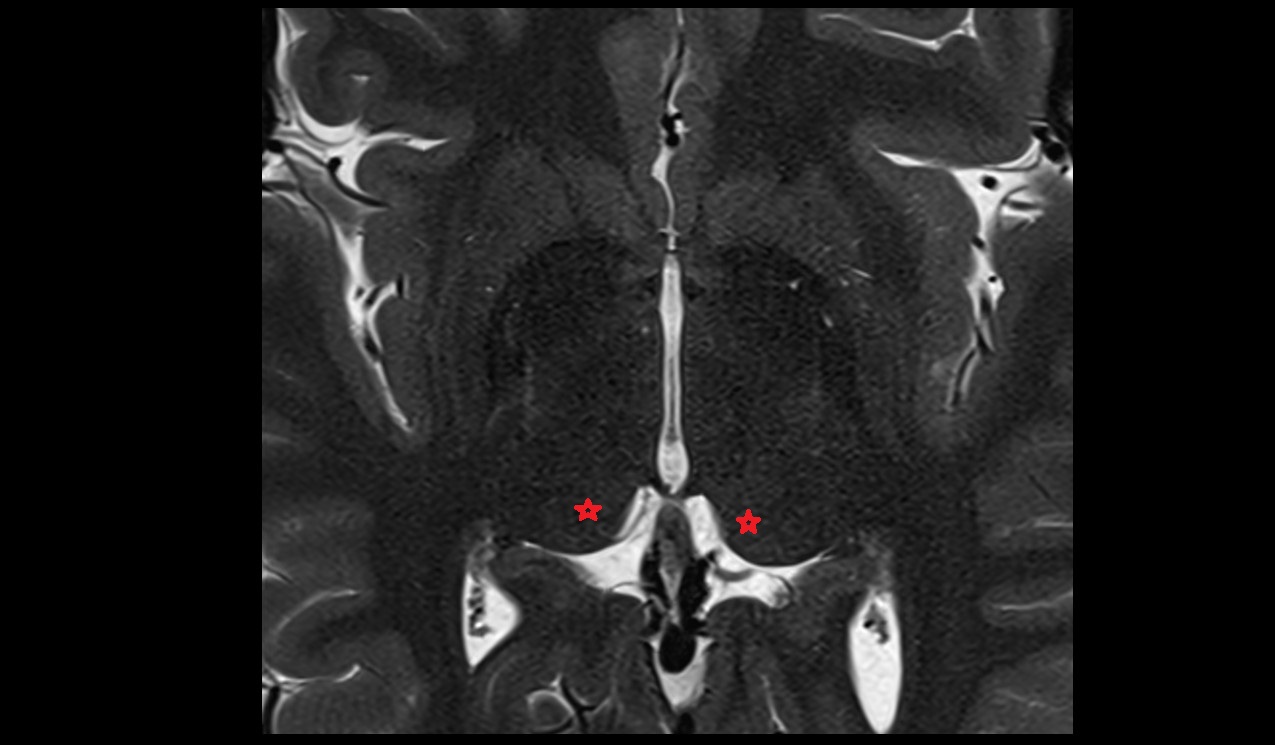

- Hippocampus